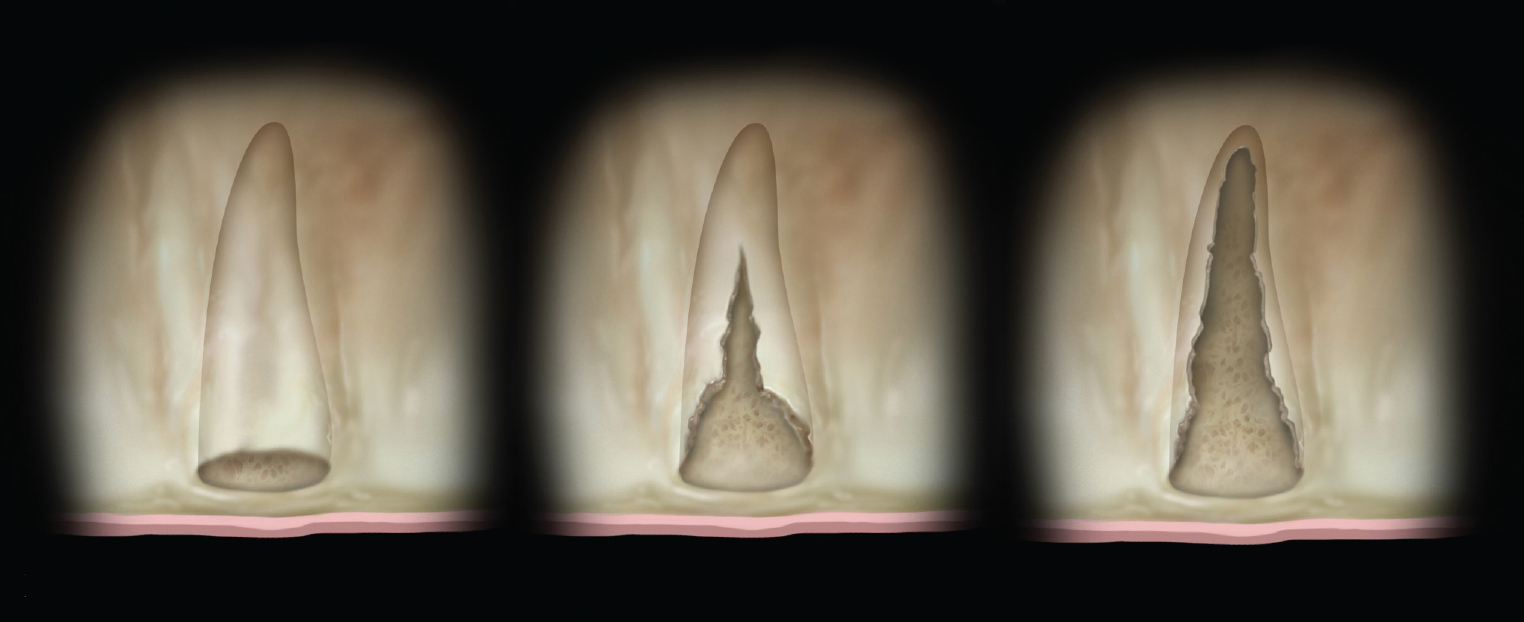

(Left) Grade I socket with an intact buccal plate demonstrating less than 25% bone loss; (Center) Grade II socket showing  ssure, dehiscence, and approximately 50% buccal plate loss; (Right) Grade III socket with more than 50% buccal plate loss.

Grade I sockets are the most ideal. Following tooth extraction, a socket that has an intact buccal plate, adequate interproximal bone, and satisfactory apical topography will fall into this category. In this classification, an intact buccal plate is defined as having no fissures or dehiscences and less than 25% loss of height (Figure 4, left; Figure 5, left). This percentage of buccal plate loss was selected as the cutoff based on the average root length of single-rooted teeth, which is 14.2 mm,25 and the amount of buccal plate that can be reliably regenerated during immediate implant placement. Adequate apical topography is defined as enough bone present apical to the extraction site to allow for engagement of 3 mm to 4 mm of a properly positioned immediate dental implant (Figure 2).1,2 Adequate interproximal bone is defined as no or mild (up to 2 mm) periodontal bone loss on the adjacent teeth as to allow for support of the interproximal soft tissue and to enable placement of the platform of an immediate implant in the proper apical-coronal position relative to the adjacent teeth while still being bordered by bony walls on the mesial and distal aspects26 (Figure 3, left).

Grade II sockets are differentiated from Grade I by the amount and quality of the remaining buccal plate. A Grade II socket has a fissure, dehiscence, or deficiency of the buccal plate totaling a 25% to 50% loss. Like Grade I sockets, they have adequate interproximal bone and apical topography (Figure 3, left; Figure 4, center; Figure 5, center).

Grade III sockets are the most deficient and include any socket with inadequate apical topography, insufficient interproximal bone, or more than 50% loss of buccal plate. Inadequate apical topography is defined as not enough bone present apical to the extraction site to allow for implant placement and may be the result of bone loss caused by periapical lesions or concavities due to existing anatomy of the alveolus (Figure 4, right; Figure 5, right). Insufficient interproximal bone is defined as moderate-to-severe periodontal bone loss—greater than 2 mm on one or both of the adjacent teeth.